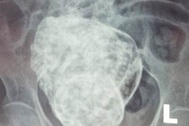

Trước đó, ngày 22/3, sau khi bị đau cột sống thắt lưng và vùng hạ vị, cụ Sáu được con cháu đưa vào Bệnh viện đa khoa Khu vực Cam Ranh để thăm khám. Tại đây, sau khi thăm khám và chụp X-quang, các bác sỹ phát hiện có hình hài bào thai nằm trong ổ bụng của cụ bà.

Kết quả chụp MRI cho thấy có khối bất thường trong ổ bụng vùng hạ vị, ở sau bàng quang, có hình dạng giống thai nhi, khả năng thai vôi hóa.Các bác sỹ nhận định đây là trường hợp thai trong ổ bụng chết lưu đã rất lâu, hóa thạch (lithopedion) và hiện đang có biến chứng gây đau dữ dội vùng hạ vị và thắt lưng.

Các bác sỹ cho biết, tuổi thai trong cơ thể cụ Sáu ít nhất là 27 năm, còn lâu nhất là khoảng 40 năm. Đây là trường hợp “thai đá” đầu tiên tại Việt Nam và hiện trên thế giới chỉ ghi nhận khoảng 300 ca.